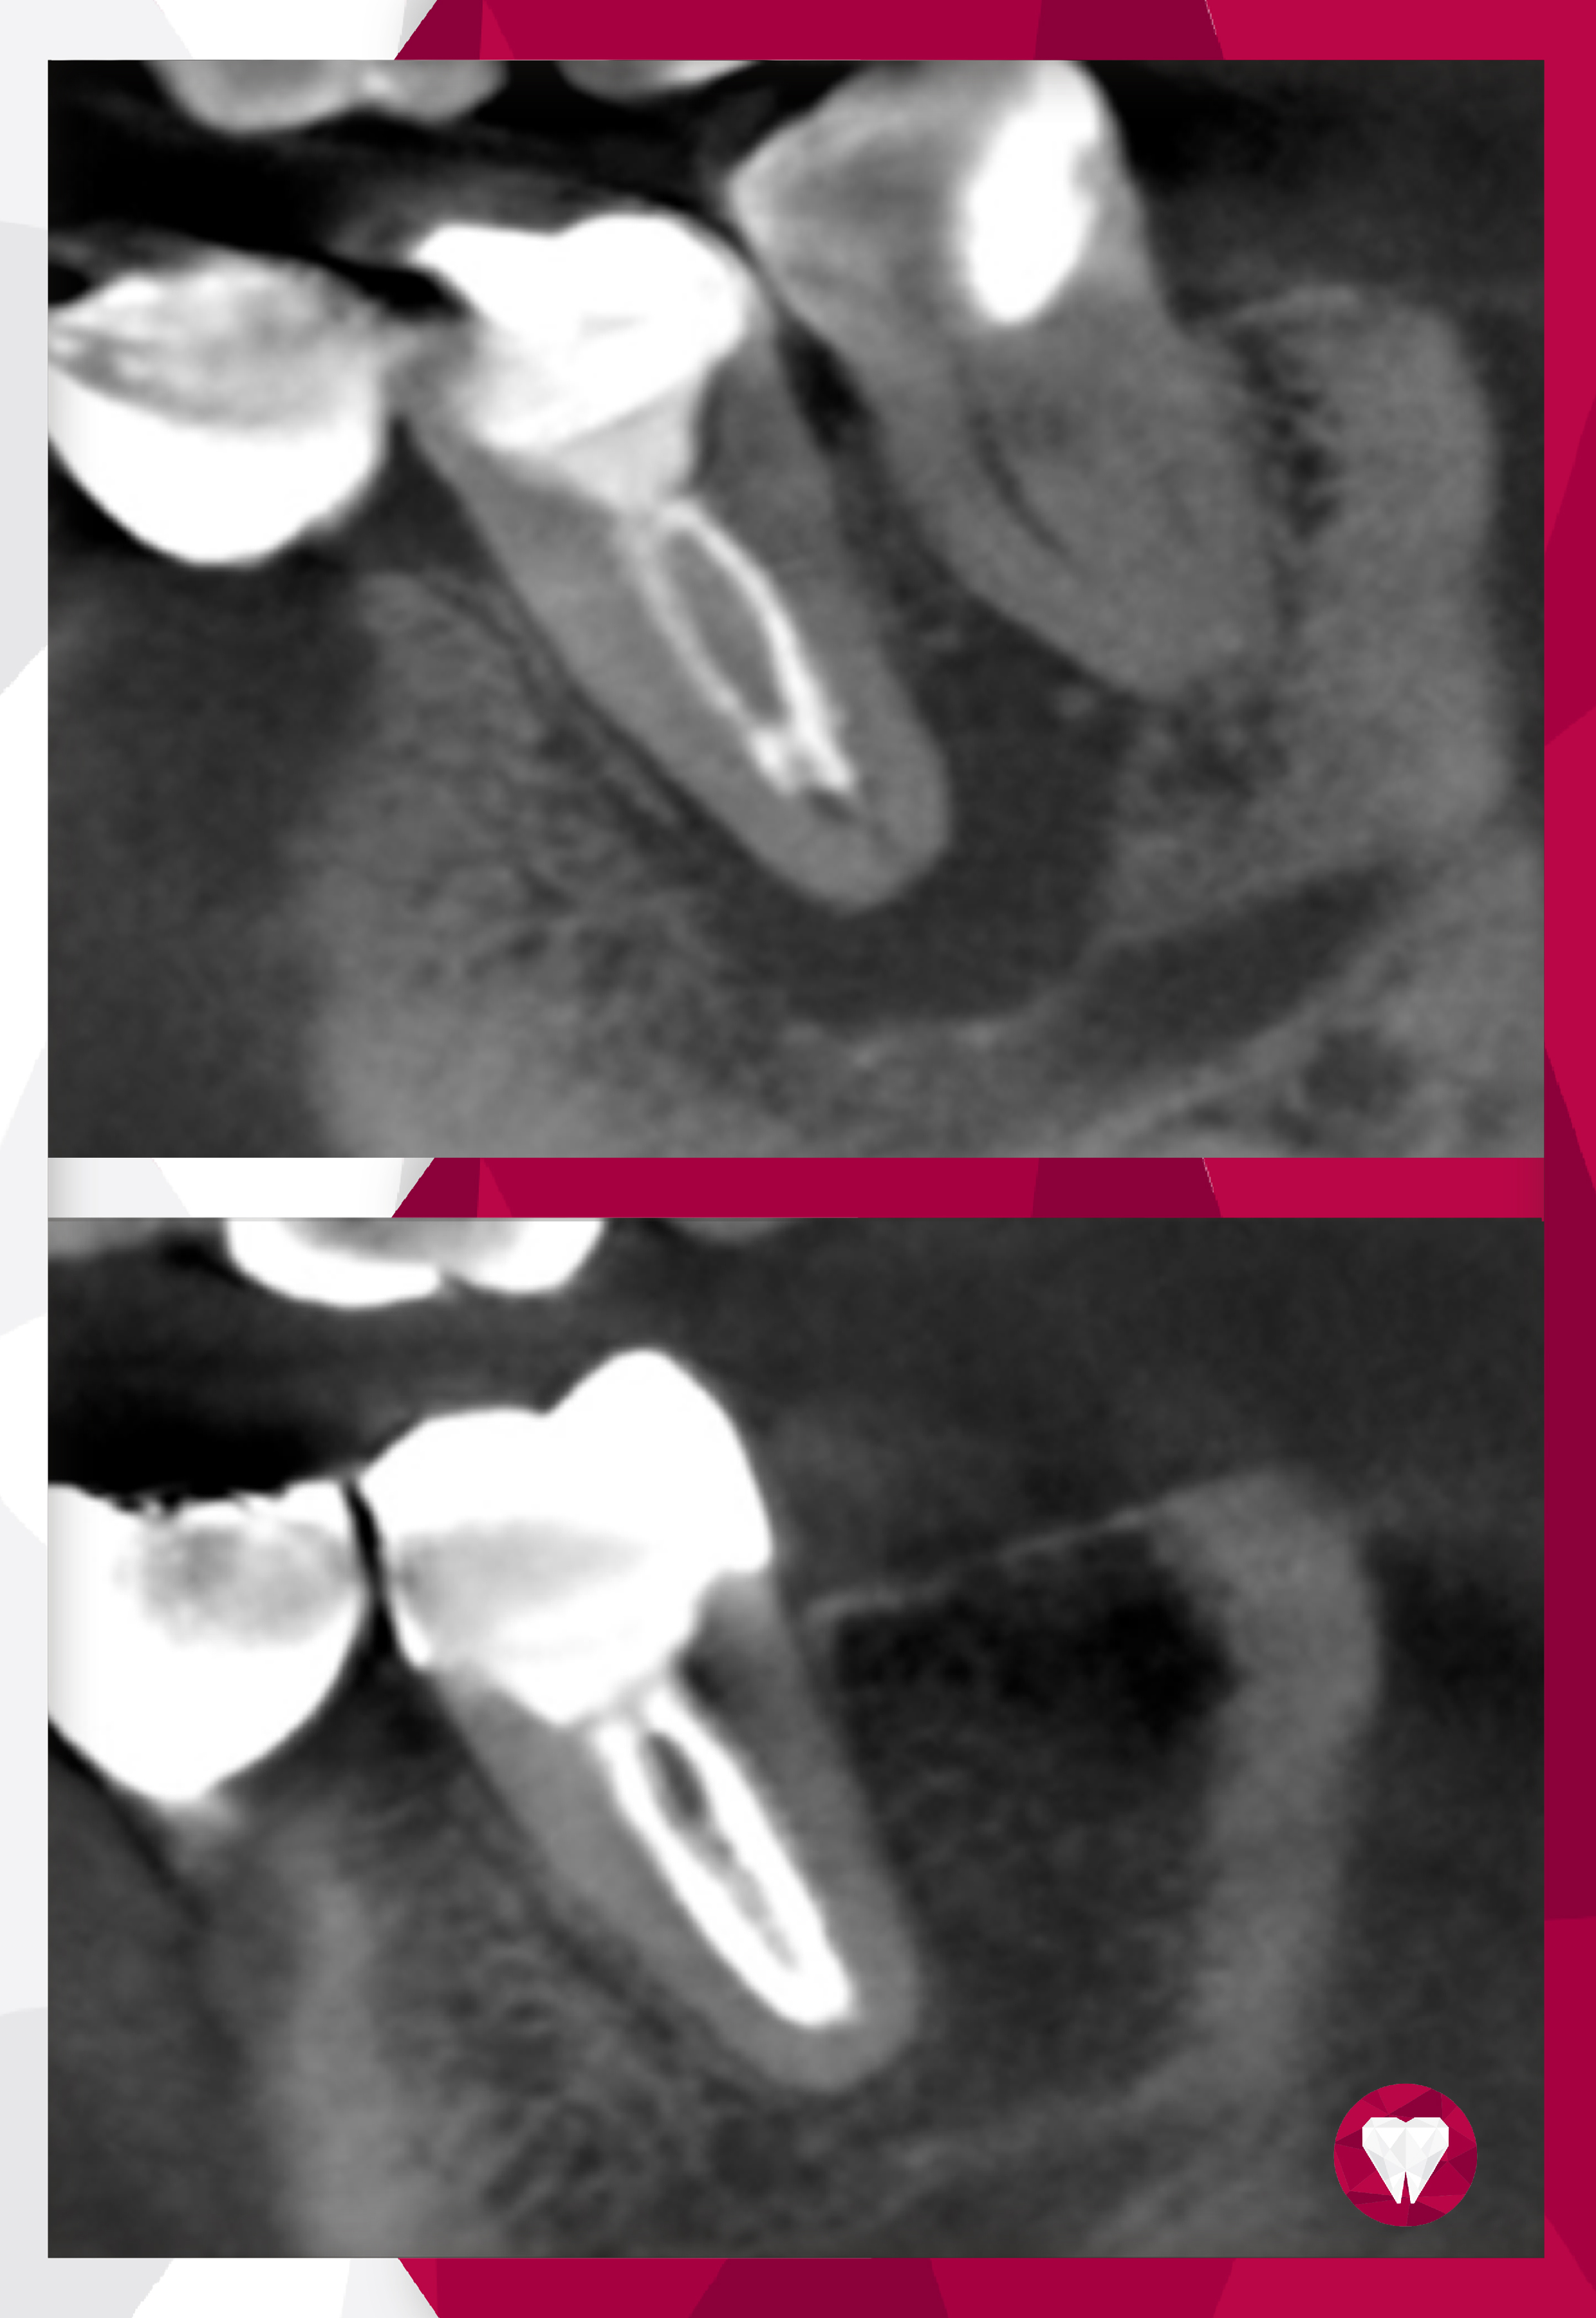

- • лечения каналов корней зубов;

- • лечение кариеса, пульпита, периодонтита;

- • хирургическая установка зубных имплантов;